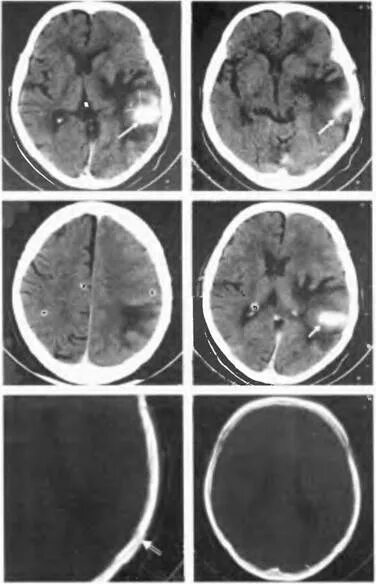

Ушиб мозга на кт